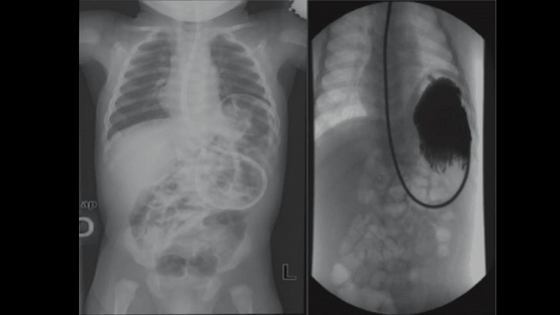

- Röntgen grafisi: Karın boşluğundaki anormal gaz birikimlerini göstererek mide burkulmasını tespit eder.

Mide volvulusunun doğru tanısı, hastanın sağkalımını doğrudan etkileyen bir faktördür. Bu bölümde, Mide Volvulusu (Mide Burkulması)'nun teşhis aşamalarını detaylı bir şekilde inceleyeceğiz. Tanı sürecinde, doktorlar genellikle fiziksel muayene ile başlar ve ardından görüntüleme teknikleriyle durumu netleştirir. Bu yöntemler, hem hızlı hem de güvenilir sonuçlar sağlar.

Öncelikle, fiziksel muayene sırasında doktorlar karın bölgesini dikkatle inceler. Daha sonra, şu tanı araçları sıkça kullanılır:

Bu tanı yöntemlerini uygulamak, Mide Volvulusu (Mide Burkulması)'nun hızlı bir şekilde doğrulanmasını sağlar. Tecrübelerime göre, erken teşhis edilen vakalarda başarı oranı oldukça yüksektir. Okurlarım, bu süreçte doktorlarıyla açık iletişim kurarak doğru tanı almanın yollarını öğrenmelidir.